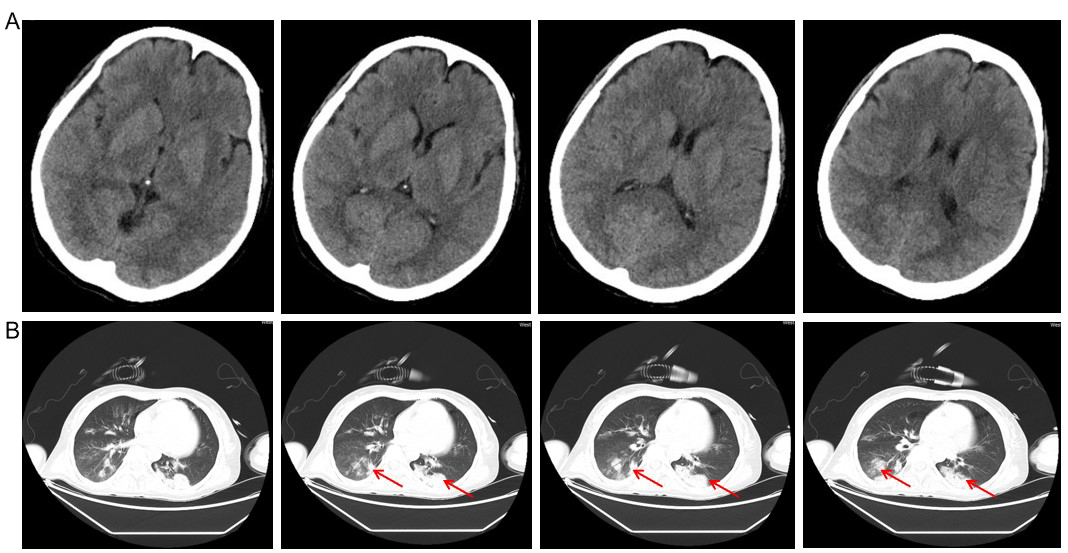

转入本院后即刻给予患者行急诊生化检查。血常规: 白细胞计数13.60×109/L、中性粒细胞% 86.0%、血红蛋白99.0 g/L、血小板计数141.0×109/L。肝肾功能: 白蛋白39.5 g/L、谷丙转氨酶177 U/L、谷草转氨酶207 U/L、总胆红素60.4 μmol/L、直接胆红素20.0 μmol/L、间接胆红素51.1 μmol/L、血氨83 umol/L、尿素6.12 mmol/L、肌酐57.2 μmol/L、尿酸566.3 μmol/L。电解质: 钾4.00 mmol/L、钠140.2 mmol/L、氯108.6 mmol/L、钙2.16 mmol/L、磷0.73 mmol/L、镁1.06 mmol/L。凝血功能:PT 20.3 s、INR 1.83、APTT 27.6 s、FIB 1.47 g/L。因患者病情危重,经与患者家人沟通后转入重症监护室治疗。患者既往有“剖宫产”手术史6年,胆囊结石及皮肤湿疹病史2年。否认肝炎、心脏病、酗酒及精神心理疾病病史。入院查体:体温36.7℃、呼吸频率15次/min、心率74次/min、NBP 121/67 mmHg(1 mmHg=0.133 kPa)、SPO298%(FiO240%)。格拉斯哥评分E1M3V1,皮肤巩膜无黄染,浅表淋巴结未触及,未见肝掌及蜘蛛痣。口腔未闻及异常气味,口腔黏膜无灼伤,口角无偏斜。双侧瞳孔等圆等大约2 mm,对光反射迟钝。颈软,气管居中,三凹征阴性。胸廓无畸形,双肺可闻及湿啰音。心率74次/min,律齐,各瓣膜区未闻及异常。腹彭隆,下腹部可见陈旧性手术疤痕。肝脾未及,肠鸣音减弱。四肢肌张力正常,肌力检查不配合,病理征及脑膜刺激征阴性。完善头胸CT(图 1)及实验室检查(图 2、3)。诊断: ①急性杀虫剂中毒(丁醚脲); ②中毒性肝衰竭; ③肝性脑病; ④吸入性肺炎。予导泄、利尿、抑酸护胃、保肝、血液灌流(HA230, 每次2 h)、抗感染、降血氨等综合治疗。2021年6月3日09:00患者深昏迷、无尿、外周指脉氧约80%(面罩吸氧)。动脉血气分析pH 7.27、PCO2 32 mmHg、BE -12.2 mmol/L、HCO3-14.7 mmol/L、Lac 7.6 mmol/L。谷丙转氨酶14 213 U/L、谷草转氨酶 >15 000 U/L、总胆红素79.9 μmol/L、直接胆红素66.1 μmol/L、间接胆红素25.3 μmol/L、尿素8.14 mmol/L、肌酐167.3 μmol/L、血氨473 umo/L、LDH>20 000 U、cTnI 0.52 ng/mL。予气管插管有创辅助通气[7.5号气管导管,经口可视喉镜气管插管,插管深度为距离门齿23 cm;ASV通气模式,FiO2100%、PEEP 5 cmH2O(1 cmH2O=0.098 kPa)]、床旁血液灌流(健帆血液灌流机,HA230,吸附剂树脂,初始引血速度100 mL/min,目标血流速度180 mL/min,治疗时间2~3 h)联合CVVHDF(Fresenius,治疗剂量25 mL/kg•h,目标血流速度180 mL/min,置换液流速1 000 mL/h,前稀释,低分子抗凝,负荷剂量60~80 IU/kg,维持剂量4~6 IU/Kg,治疗时间12~24 h)等治疗。第6天脱机拔管,一般情况好转(图 2、3),第8天康复出院。出院后1周、1月及半年随访患者健康状况良好,完全恢复日常生活。

| A: 头部CT提示未见异常;B: 胸部CT,箭头所示双肺感染 图 1 头胸部CT平扫情况 |

本例患者中毒特点是病程进展迅速,中毒1 d后即出现意识障碍,与郑武洪等[1]报道病例虽相似却又有所不同,不同处在于后者案例含有甲氨基阿维菌素,患者意识障碍为甲氨基阿维菌素的中枢神经系统损害作用所致[4]。本案例虽早期也出现意识障碍,可头部CT检查却无异常发现(图 1A),患者短时间内出现意识障碍其具体原因不清,可能与靶器官肝脏受损血氨升高致肝性脑病相关,也可能为丁醚脲潜在的中枢神经系统损害相关所致。目前,丁醚脲是否具有中枢神经系统损害作用尚无相关研究。本案例中毒2~4 d后即出现心脏、肝脏、肾脏、凝血功能、造血功能等多个器官功能障碍(图 1~3),其中尤以肝功能损害为重(图 3)。研究发现,甲氨基阿维菌素和丁醚脲混合中毒可在病程早期出现休克、多器官功能障碍、代谢性酸中毒等,肝酶可在中毒后第3天升高达高峰[1],此案例与之类似。但罗醒政等[5]研究发现,肝酶异却多在中毒后第4~5天达峰,其原因可能与丁醚脲独特的肝脏损害机制有关[6],有待进一步对其具体肝毒性分子机制进行深入研究。本例患者病程早期即出现高乳酸血症(图 2A),一方面,可能与丁醚脲具有抑制有氧代谢作用相关[7],致使三羧酸循环代谢通路异常,乳酸堆积。另一方面,可能为丁醚脲的肝毒性作用,肝功能受损后乳酸清除障碍。机体严重感染会导致造血抑制,进而引起血小板减少[8],血小板减少的程度可间接反应炎症反应的危重程度[9]。本病例患者在起病第3~4天炎症反应达高峰(图 2B),可能与患者昏迷误吸致吸入性肺炎肺部感染加重有关(图 1B)。受炎症反应影响,血小板也在此时间段内降到最低。此外,也可能为丁醚脲中毒本可导致血小板减少[10]。病程后期血小板逐步回升(图 2C),一方面,患者肺部感染得到了控制。另一方面,血液灌流及血液净化及时清除了毒性成分及炎性因子。除了肝功能、有氧代谢及造血功能受损以外,心肌及凝血功能也有受损(图 2D、E、F),并且表现出与上述靶器官受损类似的特点。部分原因为此阶段炎症瀑布反应所致,也可能是丁醚脲对心肌及凝血功能的损害作用导致,其具体机制不清,有待进一步研究。